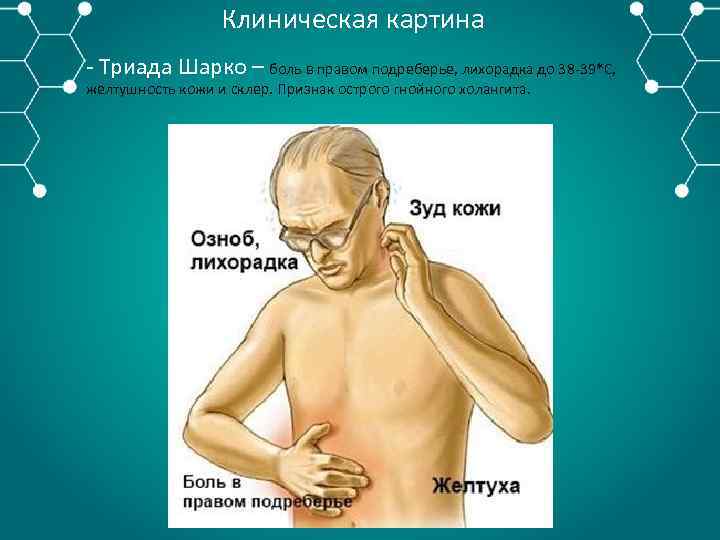

Клиническая картина Триада Шарко – боль в правом подреберье, лихорадка до 38 39*С, желтушность кожи и склер. Признак острого гнойного холангита.